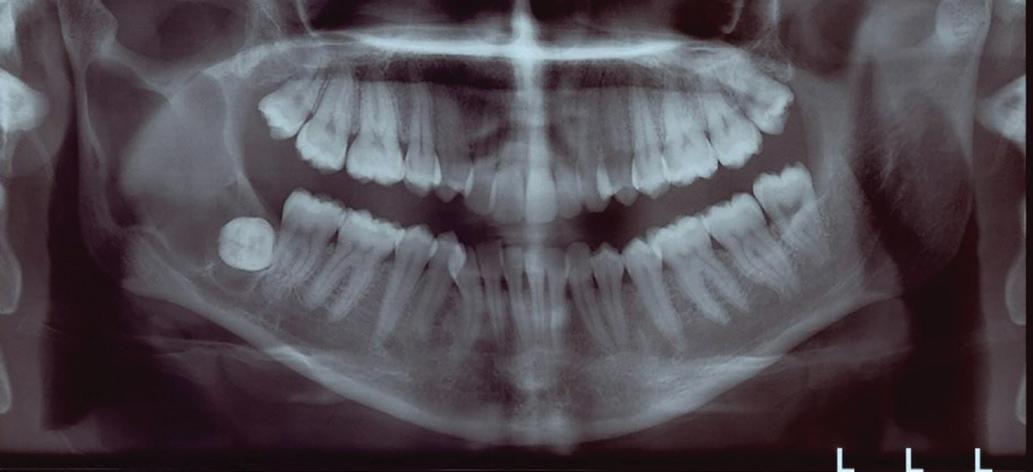

Chu44 35 M Swelling on left side of cheek FP,

Ferreira et al45 19 F Moderate headache, nausea, vomiting, left facial hypesthesia, low visual acuity FP, PP

Sohal et al46 24 M Massive swelling in right side of face FP

Linaburg et al47 50 F Massive swelling in left side of face Acanthomatous, FP

Abbreviations: F, female; FP, follicular pattern; M, male; NR, not reported; PP, plexiform pattern.

Chart. Distribution of maxillary ameloblastoma with extension into associated vital structures (N = 45).

Ameloblastomas of the jaws are commonly diagnosed in the third decade of life, and there is no sex predilection. However, ameloblastomas involving the sinuses and nasal cavities are more common in older men, as in the present case.49

Diagnosis of ameloblastoma requires clinical, radiographic, and histopathologic examinations. Clinically, sinonasal ameloblastoma can be associated with nasal obliteration, sinusitis and/or epistaxis, and less common signs and symptoms of facial swelling, headache, and tearing.42 Radiographically, primary sinonasal lesions frequently appear as radiopaque, solid lesions that fill the nasal cavity or sinus. In contrast, ameloblastoma of gnathic origin commonly presents as a unicystic or multicystic entity.42 However, this radiographic difference cannot be appreciated if the tumor involves all the vital structures and presents as a single lesion involving the maxillofacial region of that site. Histologically, ameloblastoma of jaws and sinonasal ameloblastoma have a similar appearance, commonly

Extension

Nasal cavity, orbital floor